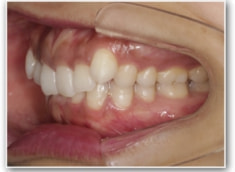

叢生+左下1番先天欠如ケース

治療法:裏側の矯正(リンガルブラケット:舌側矯正)

治療前